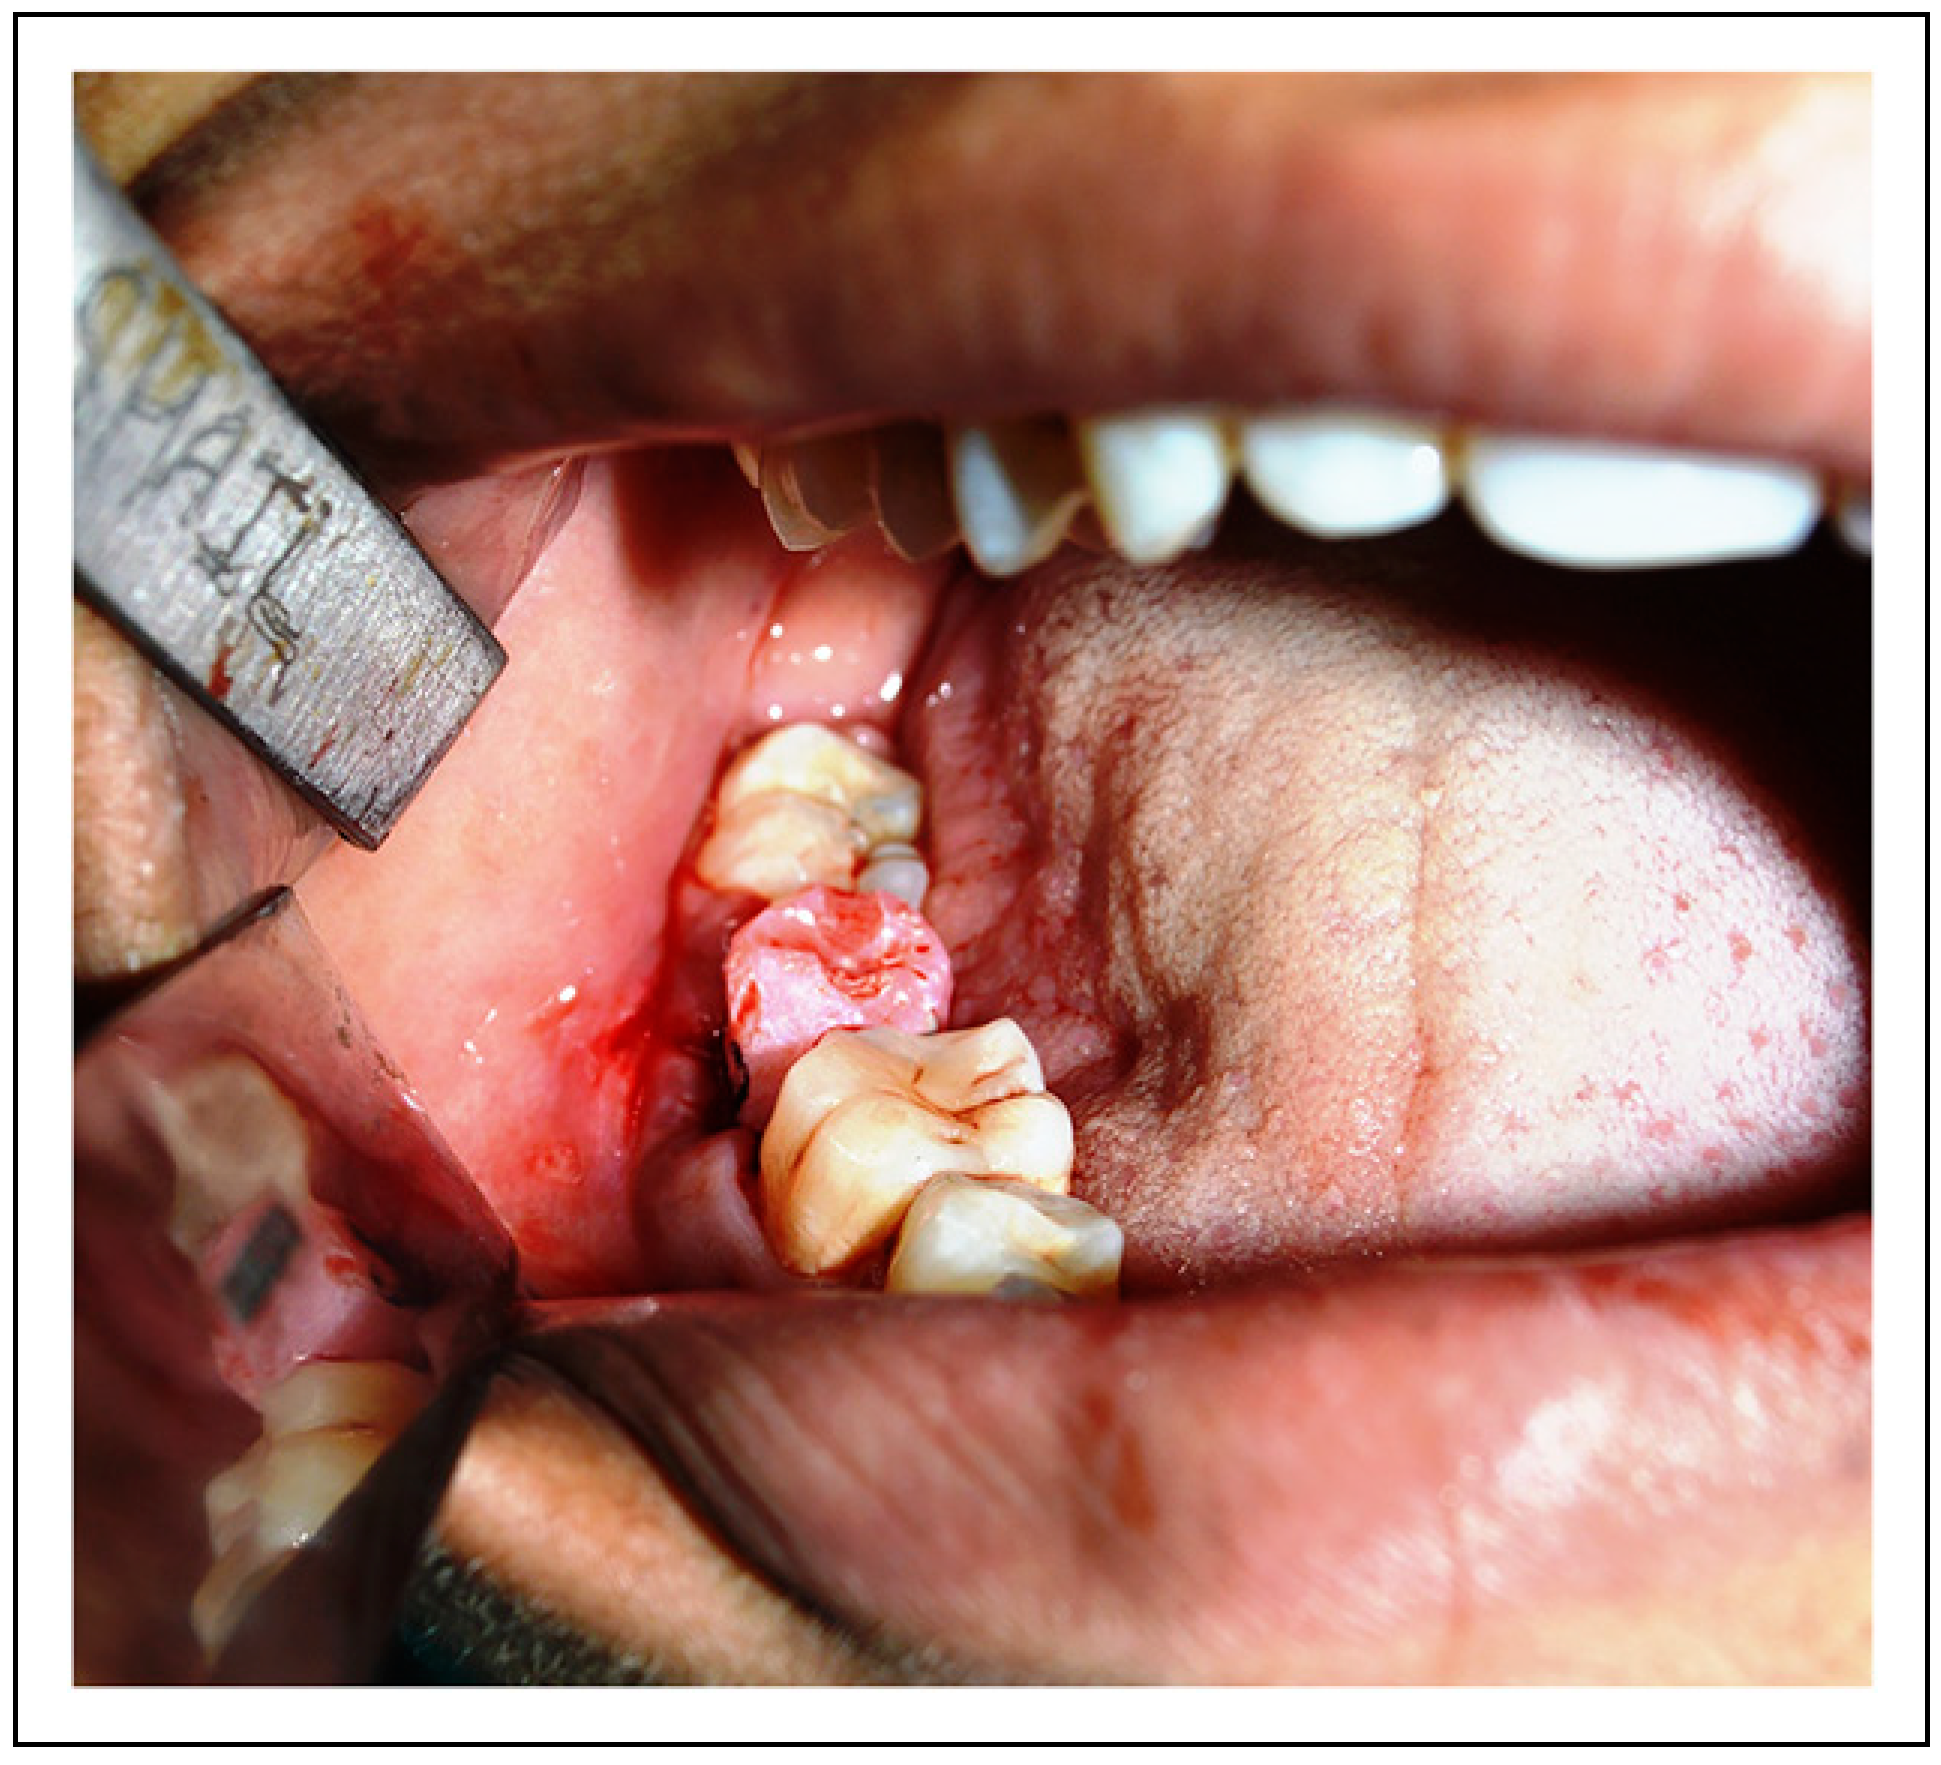

- First/second molar extraction was performed in an atraumatic manner, preserving sufficient buccal and lingual cortical plate heights (Figure 2).

- Mandibular third molar was extracted atraumatically, taking care to avoid damage to periodontal ligament in order to preserve its vitality which is essential for successful outcome of treatment (Figure 5). Simultaneously, precaution was taken not to injure the root surface, and the molar was transplanted into the prepared site with minimum possible lapse of time and less number of attempts to achieve satisfactory fit (Figure 6).